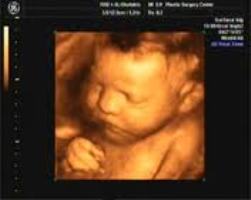

Пол виден уже с 16 недель, и вообще,девочки, ну не спешите вы так с зD узи,если нет показаний, и каких либо проблем на обычных узи приборах- его лучше делать после 30 недель, потому как можно увидеть мосичку ребенка, уже полностью сформировавшийся плод, до 30 недели, вы увидите плод, но в размытом виде, маленький он еще, много слизи и воды просвечивается.вот вам фото для сравнения, 24 и 33 неделя